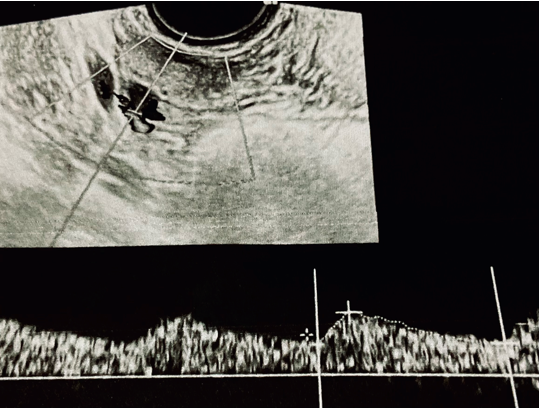

Participants: Trying to insert complete data, we excluded from the selection: pregnant women, lost to follow up women and women who initially accepted but afterwards refused to participate. After the above considerations from an initial sixty nine PCOs group, we selected thirty four PCOs italian nulliparous women that were considered for the data analysis. Cases were compared to data taken from a women control group paired by age and nulliparous status. The mean age was 31.4 years old. Patients underwent a Myoinositol (2000 mg) plus ALA (400 mg) regimen twice a day in a continued fashion in a twenty four months continuous period. Ultrasound examinations included ovarian arteries evaluation by means an endocavitarian high frequency probe (Siemens Elite NX 3) within a restricted color flow window, studying the resistance index for statistical analysis (Figure 1), ultrasound and clinical evaluations were coincident with the fifth day of menstrual period and were set as follows: Time 0 (first evaluation), Time 12 (after twelve months) and finally Time 24 (after 24 months). Ethical approval was obtained at the trial site after a decision of the operative ethical committee (CDA 0013_19) and all women accepted participation signing an individual written informed consent. Statistical analysis: Statistical data was analyzed by means of the Open Stat program (Softonic) and the Jamovi Project 2021 Statistical Software (version 1.6), based meanly in paired T test analysis.

Figure 1 Ovarian artery color Doppler waveform assessed by endocavitarian probe, in the fifth day after starting menses.